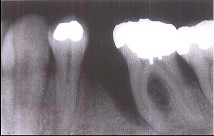

牙槽骨垂直型吸收的特点,除外 ( )

牙槽骨不发生水平方向的吸收

牙槽骨发生垂直或斜型方向的吸收

与牙根面形成角型的骨缺损

牙槽嵴高度降低不多,而牙根周围的骨吸收较多

垂直吸收多形成骨下袋

A